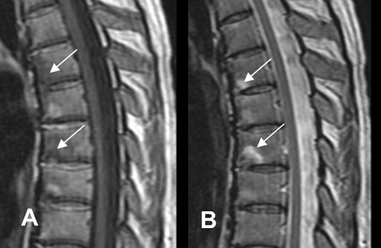

Fig 59 D. Lesiones Romanus.

A: RM sagital en T1 y B: RM sagital en T1 STIR con contraste. Lesiones en las esquinas de las vértebras, hipointensas en T1 y con realce del contraste, por lesiones Romanus de evolución aguda. En la parte anterior de L5, hay otras lesiones hiperintensas en T1 y sin realce, por depósito graso.

Fig 59 E. Lesiones Romanus.

A: RM sagital en T1 y B: RM sagital en T2. Lesiones en las esquinas de las vértebras, hiperintensas en ambas secuencias, por lesiones Romanus con depósito graso.